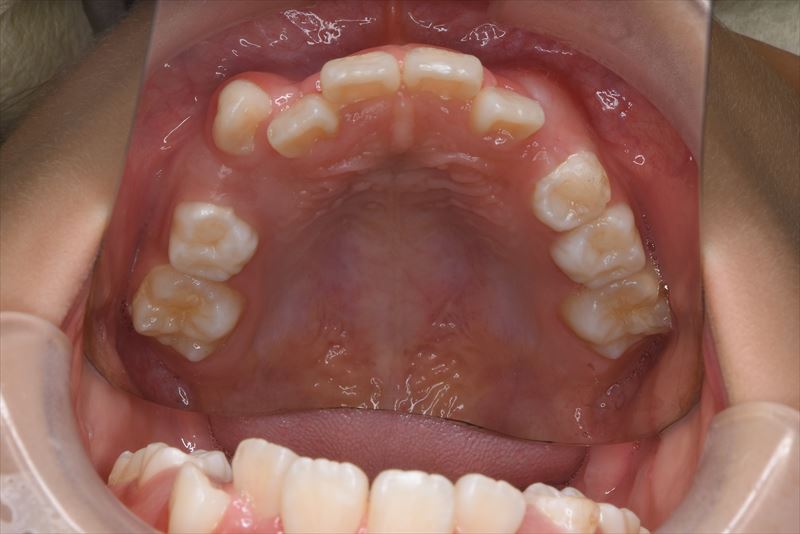

治療前

- 両側2番クロスバイト、叢生

- 両側2番にクロスバイトを認めた。排列にスペースは十分と判断し、前歯部にブラケットを装着し排列した。今後は骨格的にはⅢ級傾向であるため、必要に応じて装置を追加する予定である。